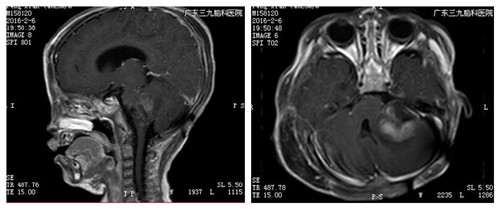

完善术前相关检查,小儿神经外科在全麻下为其进行“左侧乙状窦后入路桥小脑角占位性病变切除+ICP探头置入术”,手术顺利,术后滔滔的麻醉清醒,可自主活动,对光反射灵敏。引流管固定通畅,并予预防感染、营养支持等对症支持治疗。术后转肿瘤综合治疗中心实施放疗,再化疗的治疗方案。病理结果:髓母细胞瘤(WHO IV级)。

▲术后